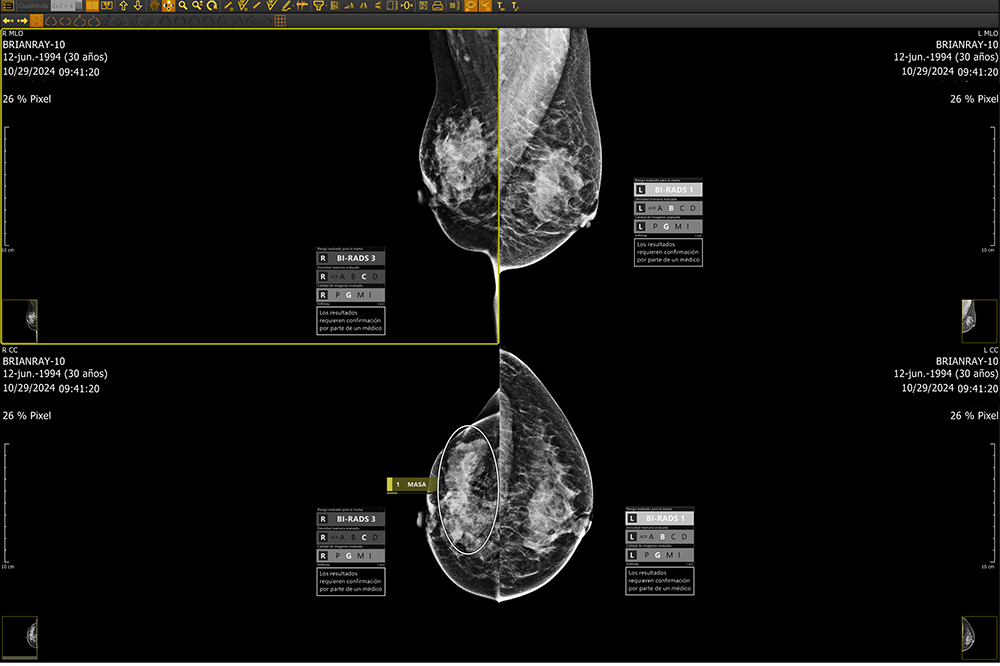

Whether deployed on-site or via the cloud, brAInray® seamlessly integrating with any PACS system, brAInray® analyzes full-field digital mammograms (FFDM) to detect and mark suspicious regions—highlighting calcifications, masses, asymmetries, and architectural distortions. It categorizes findings using ACR BI-RADS® standards and delivers automatic structured DICOM reports for clear, consistent clinical insights.